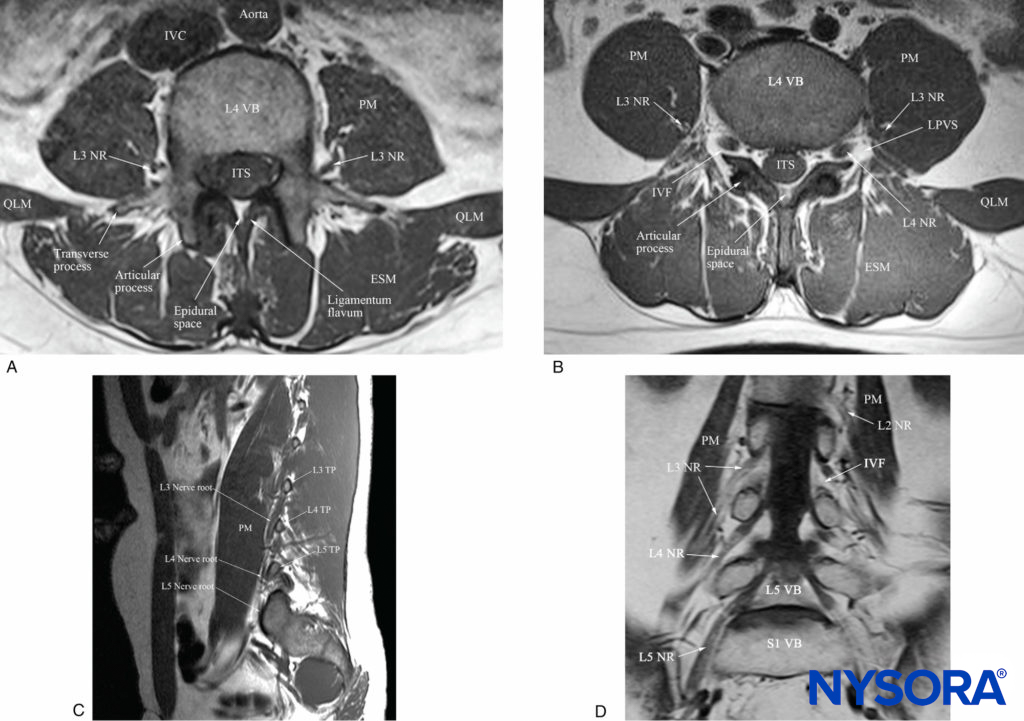

FIGURE 4. Multiplanar cadaver anatomical sections showing the anatomical relation of the lumbar nerve root and lumbar plexus to the psoas muscle (PM). (A) Cross-section through the L4 vertebral body and transverse process, corresponding to the level at which the paramedian transverse oblique scan at the level of the transverse process (PMOTS-TP) is performed. (B) Cross-sectional cadaver anatomical section from just inferior to the L4 transverse process and through the lower part of the L4 vertebral body, corresponding to the level at which the paramedian transverse oblique scan through the intertransverse space and at the level of the articular process (PMOTS-AP) is performed. (C) Sagittal cadaver anatomical section showing the relation of the lumbar plexus to the transverse process (TP) and PM. (D) Coronal cadaver anatomical section showing how the lumbar nerve roots, after they exit the intervertebral foramen, take a steep caudal course and enter the substance of the PM more caudally. The “reference-marker” of the Java application is seen as a “green cross-hair,” which represents the same anatomical point in the multiplanar cadaver anatomical sections. AP, articular process; ES, epidural space; ESM, erector spinae muscle; LF, ligamentum flavum; LPVS, lumbar paravertebral space; NR, nerve root; QLM, quadratus lumborum muscle; TP, transverse process; VB, vertebral body.

FIGURE 5. Multiplanar T1-weighted magnetic resonance imaging (MRI) images showing the anatomical relation of the lumbar nerve root and lumbar plexus to the psoas muscle (PM). (A) Transverse view at the level of the L4 vertebral body and the transverse process, corresponding to the level at which the paramedian transverse oblique scan at the level of the transverse process (PMOTS-TP) is performed. (B) Transverse view from just below the L4 transverse process and through the lower half of the body of the L4 vertebra and the articular process (inferior), corresponding to the level at which the paramedian transverse oblique scan at the level of the articular process (PMOTS-AP) is performed. Note the hypointense L4 nerve root as it exits the intervertebral foramen (IVF) and enters the hyperintense fatfilled lumbar paravertebral space (LPVS). Also seen in the posterior aspect of the psoas muscle is the L3 nerve of the lumbar plexus, which is surrounded by a layer or hyperintense fat and situated within an intramuscular compartment (the “psoas compartment”). (C) Sagittal view of the lumbar paravertebral region at the L3–L5 vertebral level showing the steep caudal course of the lumbar nerve roots. (D) Coronal view at the L3–L5 vertebral level showing the steep caudal course of the lumbar spinal nerves after they emerge from the IVF. ESM, erector spinae muscle; ITS, intrathecal space; IVC, inferior vena cava; LPVS, lumbar paravertebral space; NR, nerve root; QLM, quadratus lumborum muscle; VB, vertebral body.